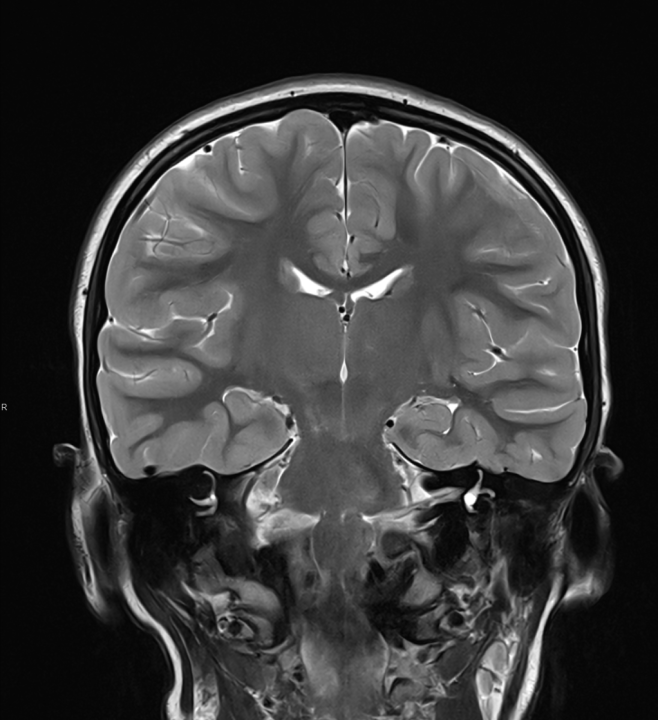

Ako su vam potrebni specijalistički pregledi mamografija, RTG, UZV, CT i MR, koji se inače koriste za dijagnostiku velikog broja zdravstvenih problema, možete ih obaviti već danas ili sutra.